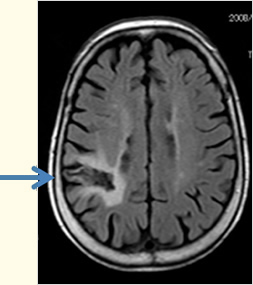

(図4)脳梗塞後遺症により、てんかん発作をおこされた患者さんのMRI(右頭頂葉に脳梗塞後の瘢痕がみられる:矢印)

(図4)